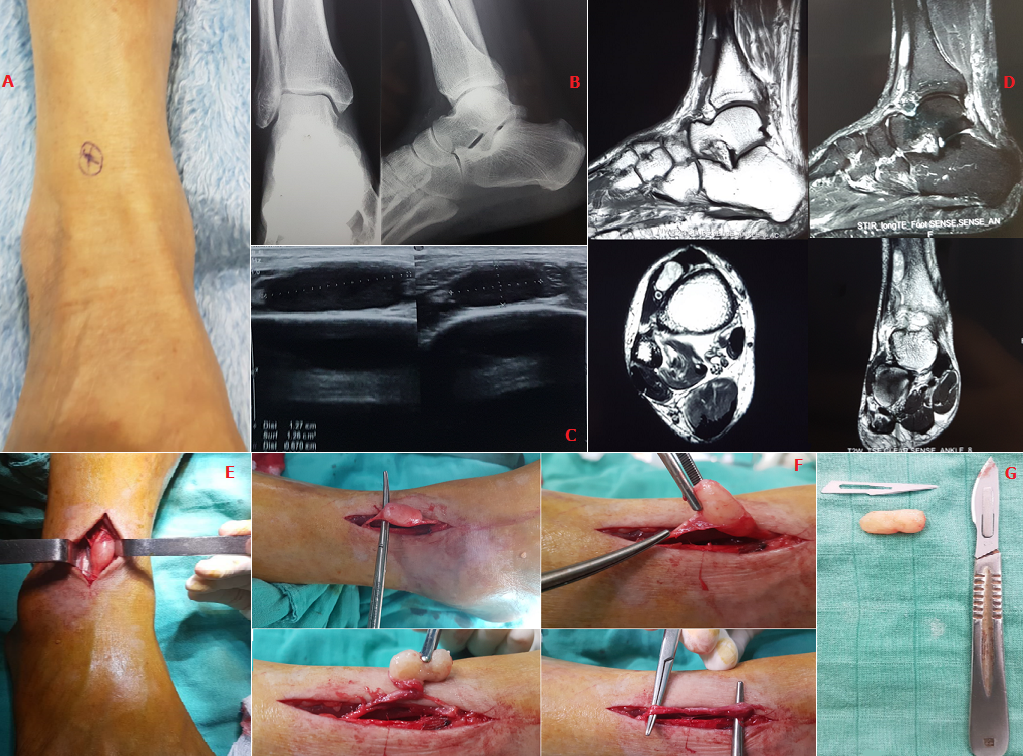

Nous rapportons le cas d'un patient âgé de 61 ans sans antécédents pathologiques particuliers. Il se plaint depuis 6 mois de douleurs avec paresthésies au niveau de la face antérolatéralede la jambe gaucheirradiant sur la face dorsale de la cheville et du pied.Ces douleurs sont exacerbées par l'effort. L'examen clinique a objectivé un déficit partiel de la sensibilité et unsigne de Tinel positif dans le territoire du nerf fibulaire superficiel (A). L'EMG a confirmé l'atteinte de ce nerf avec une diminution d'amplitude des potentiels sensitifs. Une radiographie a éliminé une cause ostéo articulaire sous-jacente (B). L'échographie a objectivé une formation tissulaire homogène bien limitée (C) et l'IRM. Une masse fusiforme centrée sur le nerf enhyposignal en T1, et hypersignal en T2 réhaussée par le produit de contraste (D). L'exérèse chirurgicale conservatrice respectant les fascicules nerveux (E, F) et l'anatomopathologie ont confirmé le diagnostic de schwannome (G) et son caractère bénin. A 1 mois de recul, le patient a vu disparaitre sa symptomatologie avec conservation de la sensibilité dans le territoire de ce nerf. En l'absence de tuméfaction, le diagnostic d'unschwannome est difficile et peut mimer un syndrome canalaire comme le cas dans notre observation. Les schwannomes sont des tumeurs nerveuses périphériques extirpables. Leur pronostic reste excellent après un traitementchirurgical adapté respectant les fascicules nerveux.